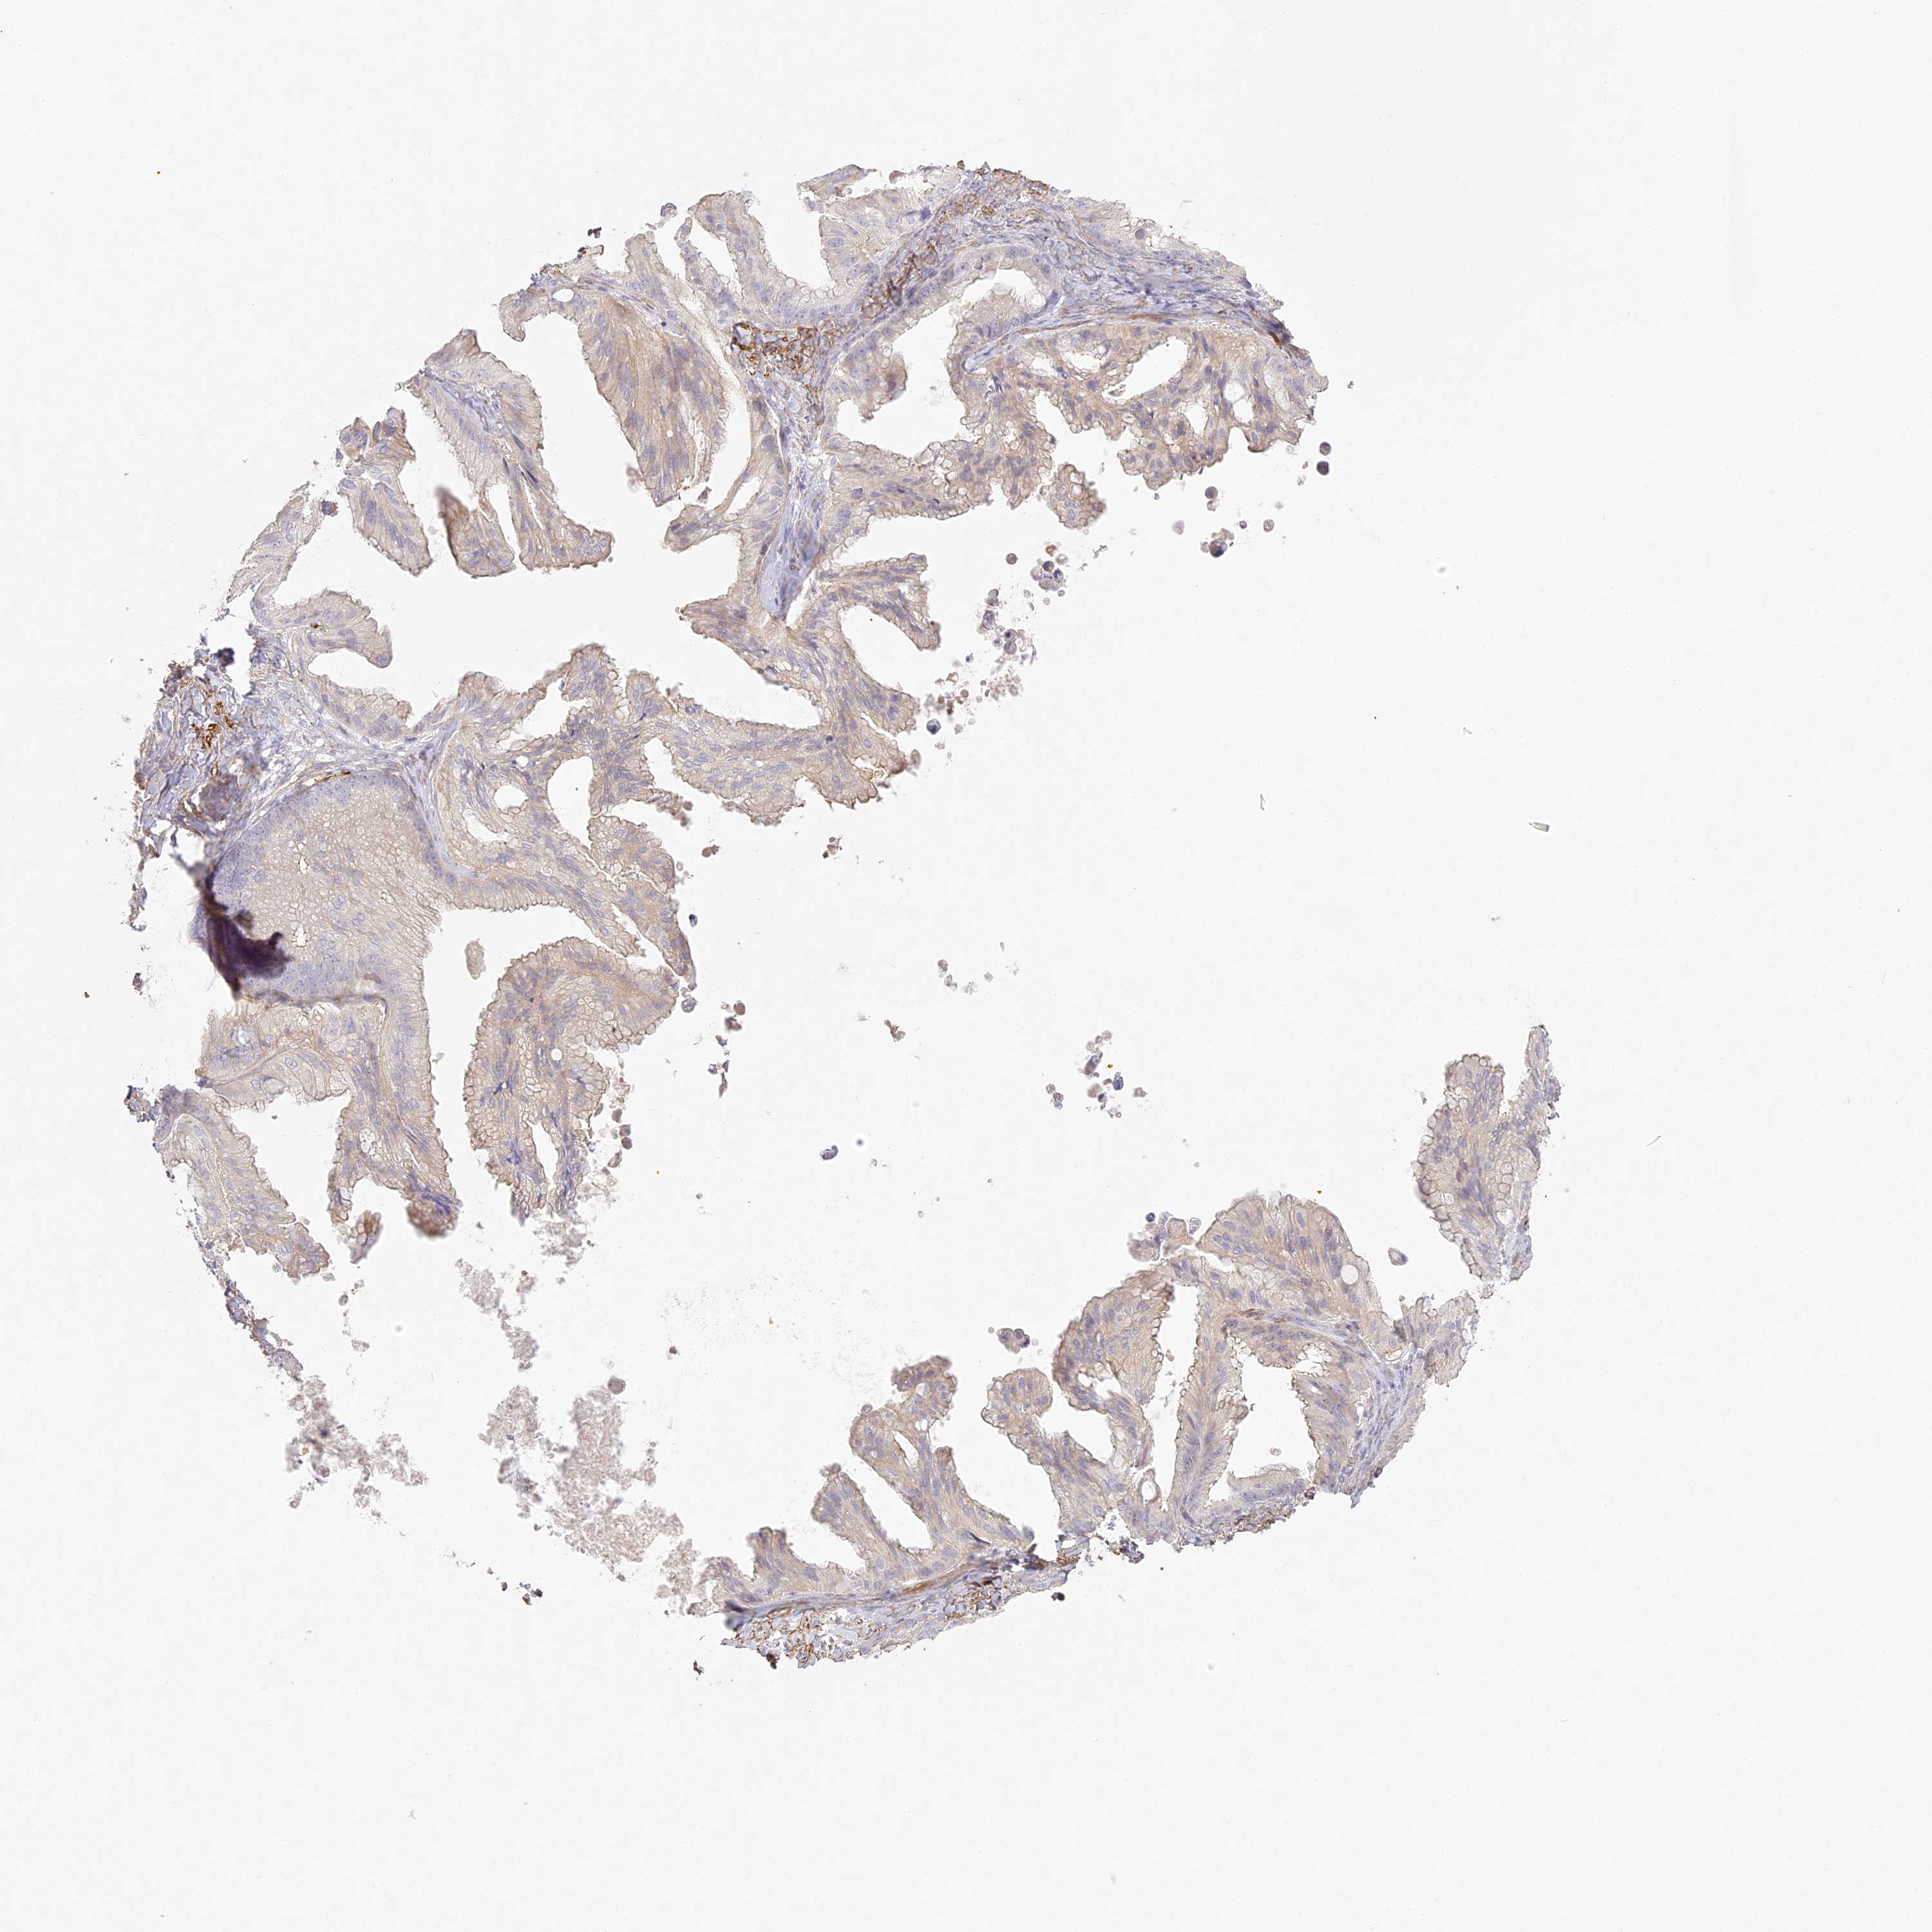

OVARIAN CANCER - Protein expressioni

A mouse-over function shows sample information and annotation data. Click on an image to view it in a full screen mode. Samples can be filtered based on level of antibody staining by selecting one or several of the following categories: high, medium, low and not detected. The assay and annotation is described here.

Note that samples used for immunohistochemistry by the Human Protein Atlas do not correspond to samples in the TCGA dataset.

Antibody stainingi

Antibody staining in the annotated cell types in the current human tissue is reported as not detected, low, medium, or high, based on conventional immunohistochemistry profiling in selected tissues. This score is based on the combination of the staining intensity and fraction of stained cells.

Each image is clickable and will lead to virtual microscopy that enables deeper exploration of all samples and also displays staining intensity scores, fraction scores and subcellular localization as well as patient and tissue information for each sample.

Antibody HPA035900

Antibody HPA035901

Cystadenocarcinoma, serous, NOS

Carcinoma, endometroid

Cystadenocarcinoma, mucinous, NOS

Carcinoma, NOS